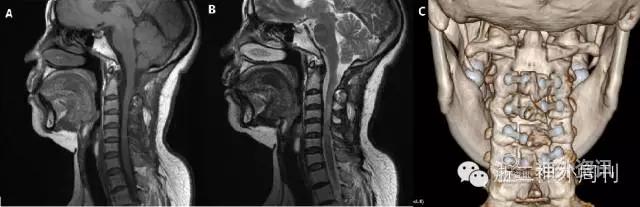

术后患者肢体疼痛症状缓解,肌力及感觉较术前无明显下降。复查MRI见肿瘤全切(图4)。术后病理诊断为“室管膜下瘤”(图5)。

图4. 术后MRI见肿瘤全切,未见残留(图A,B)。C2-5椎板复位良好(图C)。